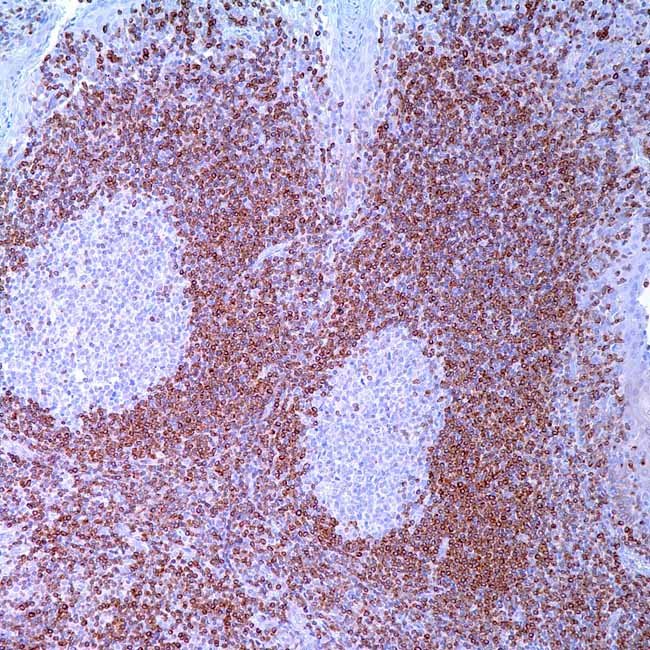

Bcl-2

The Bcl-2 family, which includes both pro-apoptotic and anti-apoptotic members, is the best-characterized protein family involved in the control of apoptotic cell death. In follicular lymphoma, Bcl-2 is a helpful marker for locating malignant cells. Antibodies specific for the Bcl-2 protein can be utilized to distinguish between reactive and malignant follicular proliferation in lymph node biopsies.

Controltonsil